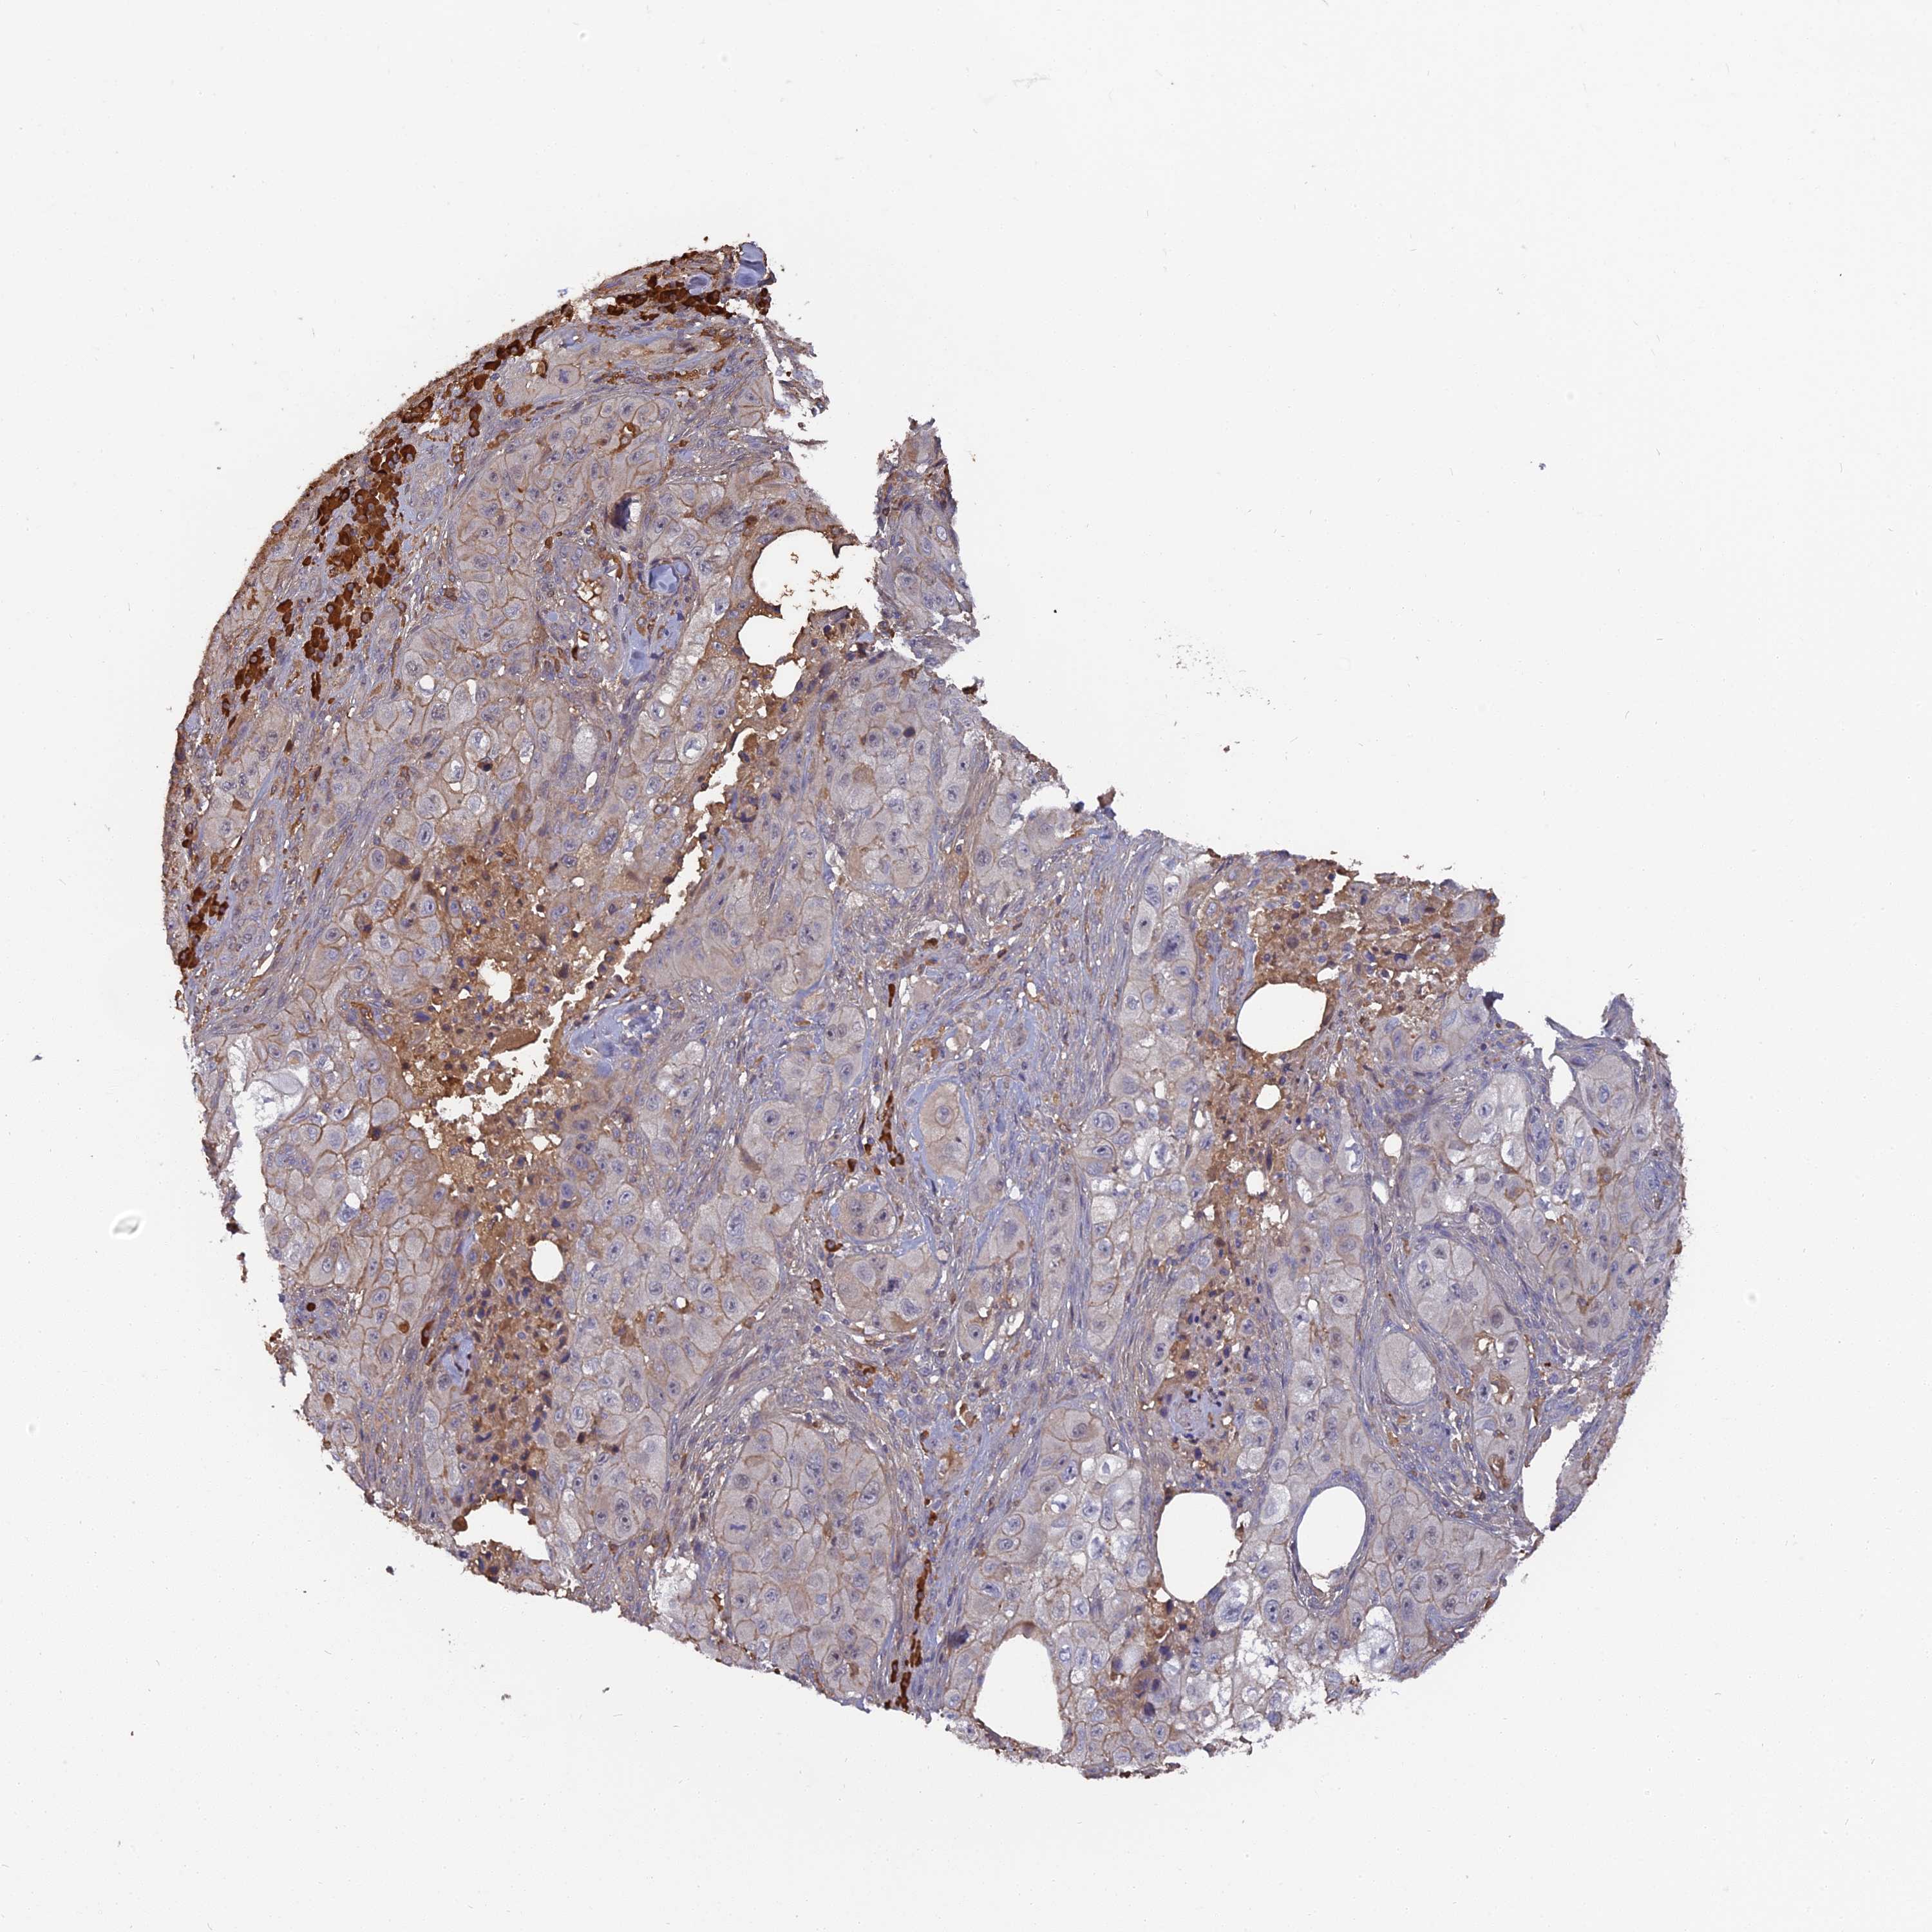

SKIN CANCER - Protein expressioni

A mouse-over function shows sample information and annotation data. Click on an image to view it in a full screen mode. Samples can be filtered based on level of antibody staining by selecting one or several of the following categories: high, medium, low and not detected. The assay and annotation is described here.

Each image is clickable and will lead to virtual microscopy that enables deeper exploration of all samples and also displays staining intensity scores, fraction scores and subcellular localization as well as patient and tissue information for each sample.

Antibody HPA042573

Basal cell carcinoma